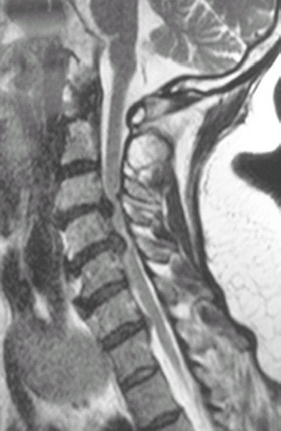

Fig.

2. Sagittal T2-weighted MRI scan showing severe stenosis at C3–C4 and

C4–C5 secondary to large disc herniations with cord signal change at

C4–C5.

MRI is used to detect and define disc

herniation, facet hypertrophy, or ligamentum flavum hypertrophy that

may be impinging on the spinal cord or cervical nerve root foramen (Fig. 2). -